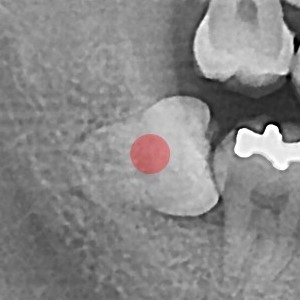

사랑니발치 20대/여성

5e20e086184bc11a2d853605b7813944_1764319753_0737.jpg